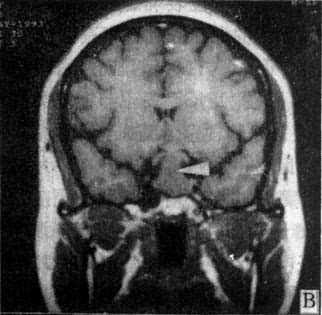

图5-1-6 MRI扫描SE序列图像

在矢状面(A)和冠状面(B)T1WI可见垂体肿块向鞍上延伸,呈等信号区(→);在横断面T1WI(C)和T2WI(D)上分别可见左枕和右基底节区脑梗塞灶呈低和高信号区(→);在矢状面T1WI(E)和横断面T2WI(F)上,可见基底动脉瘤环形影,其内为低信号和高信号区,高信号区为瘤内血栓形成(→)